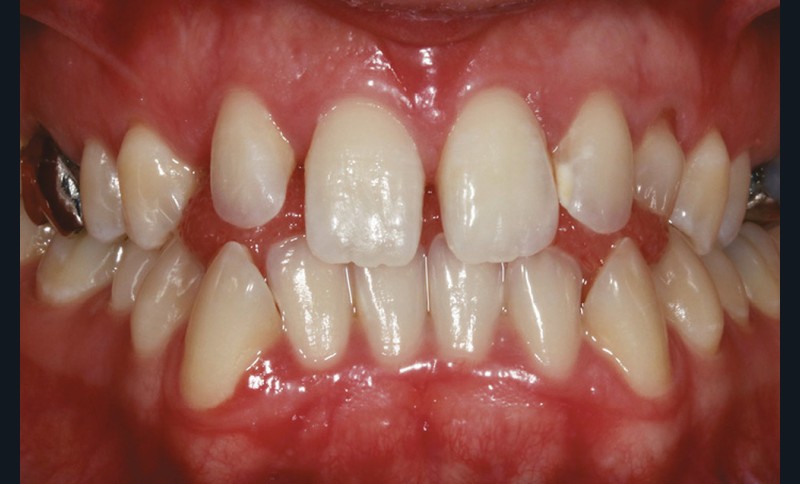

Sur le plan dentaire, on note l’absence des canines maxillaires permanentes sur l’arcade et la persistance de 63. Il existe une DDD par défaut maxillaire (indice de Bolton antérieur 90,2 %) due à l’absence des canines sur l’arcade, mais aussi à une dysharmonie de forme des dents maxillaires (fig. 2a-e).

L’examen radiologique 2D nous confirme l’inclusion de 13 et 23 en position haute, oblique en bas et en avant, couronnes en projection des apex de 11 et 21 et nous permet de quantifier le décalage squelettique (fig. 3 et 4). L‘examen radiologique 3D (cone beam) objective les rapports…